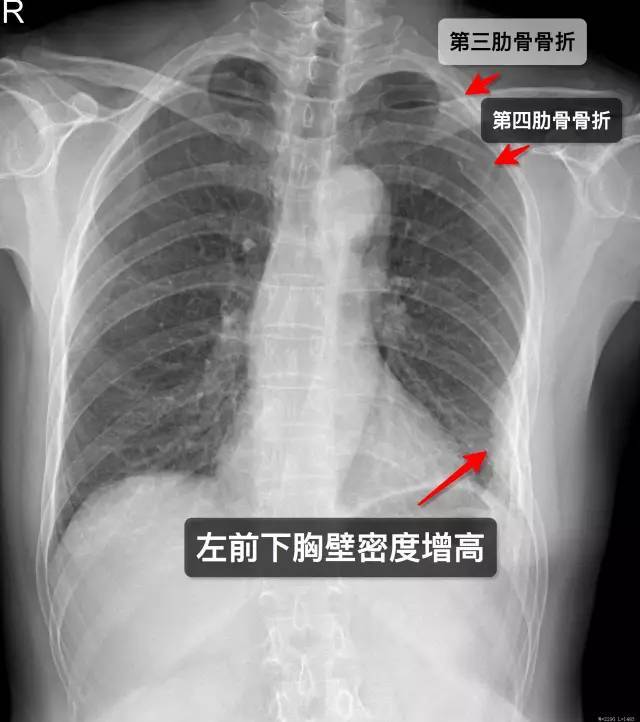

病例24肋骨骨折

图片尺寸1622x939